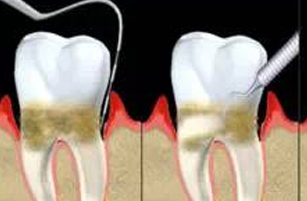

01:定期潔牙去除牙結石和牙菌斑等有(yǒu)害物(wù)質(zhì),使牙龈炎症消退

01:定期潔牙去除牙結石和牙菌斑等有(yǒu)害物(wù)質(zhì),使牙龈炎症消退 02:龈下刮治把牙龈下方的牙結石、龈下菌斑和牙周袋裏的炎性肉芽組織清除

02:龈下刮治把牙龈下方的牙結石、龈下菌斑和牙周袋裏的炎性肉芽組織清除 03:牙周翻瓣術用(yòng)手術的方法将牙龈切開翻瓣,使病損暴露後再清除結石、菌斑等

03:牙周翻瓣術用(yòng)手術的方法将牙龈切開翻瓣,使病損暴露後再清除結石、菌斑等 04:根管治療去除根管内容物(wù)對根尖周圍組織的刺激,防止根尖周病變